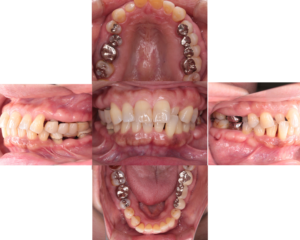

歯周病治療前 歯周病治療後